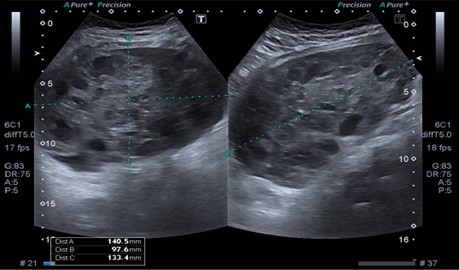

Se realizó nueva ecografía en el hospital que informa masa en topografía centro abdominal, de aproximadamente 14 x 9.7 x 13.3 cm (ver Imagen 1). El útero mide 5,5 cm en su diámetro máximo. No se logran identificar ovarios derecho o izquierdo. Se solicita radiografía de mano izquierda para valorar edad ósea la cual, según el atlas de carpograma de Oxford 2011, evidencia edad ósea de 10 años para cronológica de 8 y 3 meses.

Figura 1. Ecografía abdominal del ingreso. Se visualiza voluminosa masa en topografía centro abdominal, sólido-quística a predominio sólido de 14 x 9.7 x 1.3 cm.